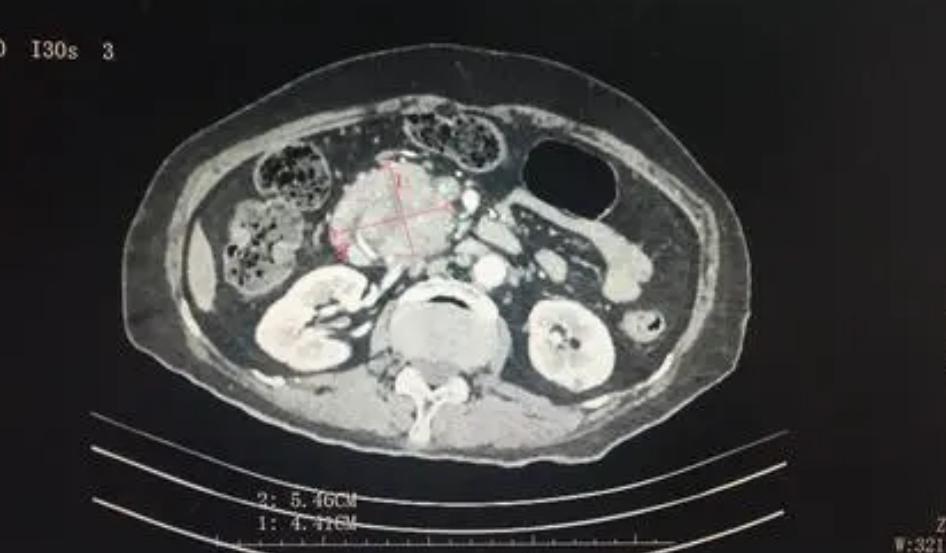

去年4月,本来只是因为一点小咳嗽,去医院做了个常规的CT平扫,没想到这一扫,黄女士竟然被AI识别成了疑似早期胰腺癌。

而医院之所以想到要用AI,是因为她的CT影像被纳入了阿里达摩院牵头的“平扫CT+AI”癌症早筛项目。

返回医院复查后,AI的判断果然是对的:胰尾部真的有肿块!

在使用对比剂进行增强扫描后,确定其大小为25×31mm。这大约是一颗中等大小的葡萄那么大。

正是因为发现得早,并很快进行了手术,黄女士才从胰腺癌这种全球生存率最低的恶性肿瘤之一的魔爪下幸存了下来。